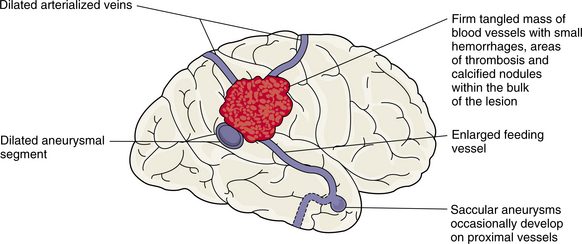

Cerebrovascular disease, the primary cause of stroke, is caused by one of several pathologic processes involving the blood vessels of the brain. The damage may be intrinsic to the vessel, or the stroke may originate remotely, such as when an embolus from the heart or extracranial circulation lodges in an intracranial vessel. The stroke may result from the rupture of a vessel in the subarachnoid space or intracerebral tissue. Fig. 32-1 shows the effects of different types of stroke on brain tissue.98

Figure 32-1 Radiographic images of the brain after stroke. A, An acute infarct with mass effect and compression of the ventricle. B, An acute intracerebral hemorrhage in the hemisphere. C, Amyloid angiopathy with acute hemorrhage; the edema surrounding the area results in a slight mass effect on the midbrain. (Reprinted from Ramsey R: Neuroradiology, Philadelphia, 1994, WB Saunders.)